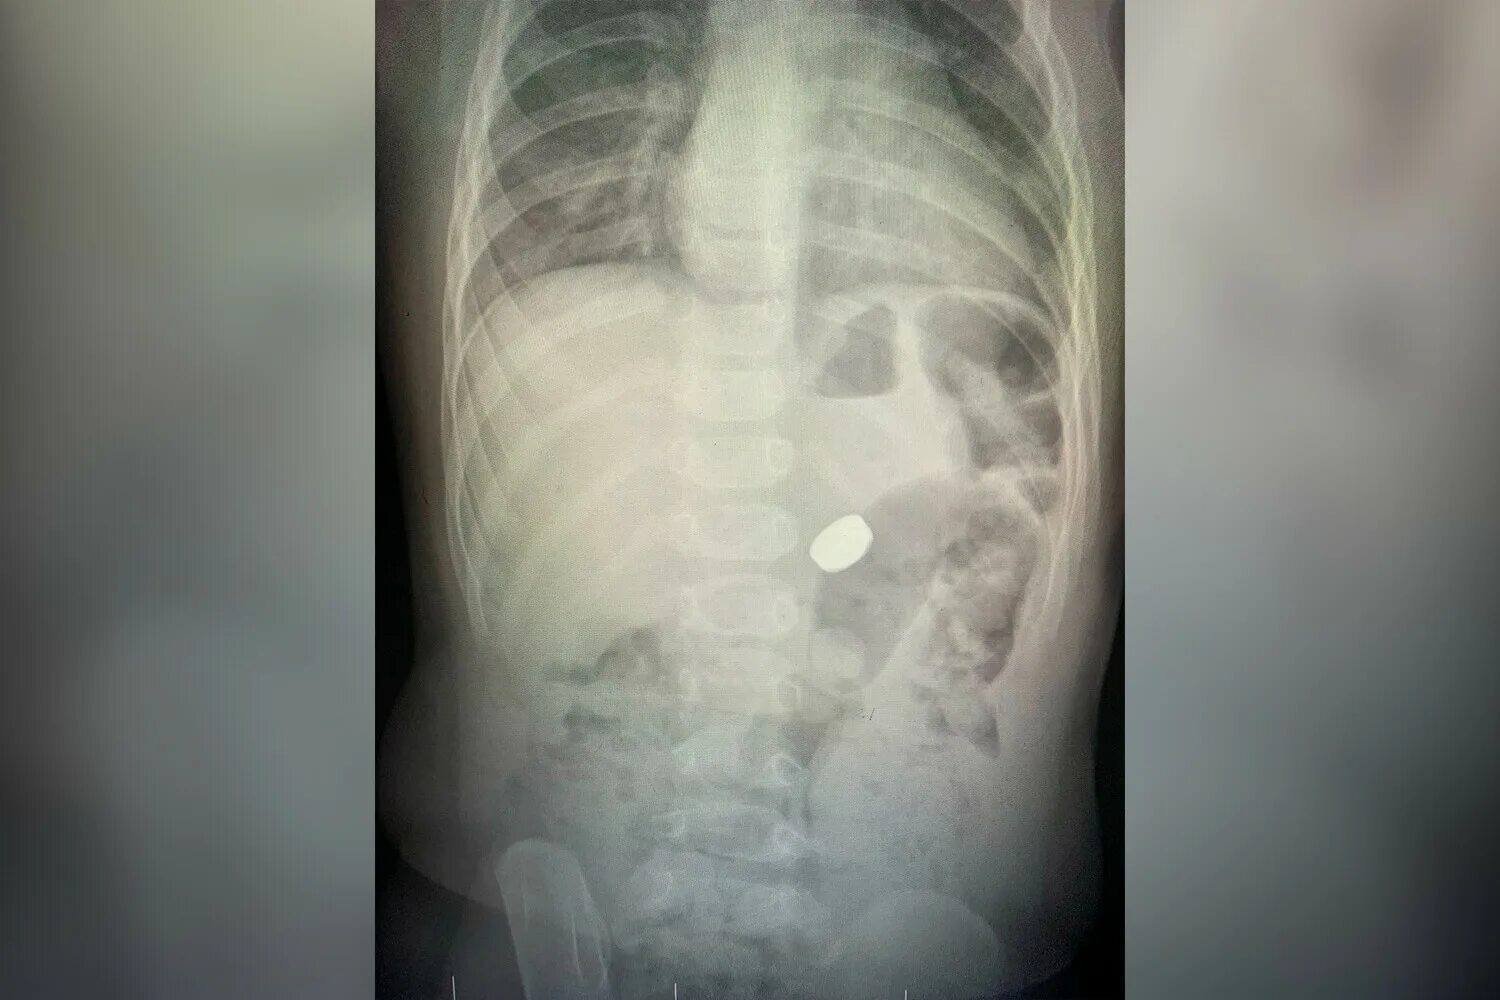

Таблетки на рентгене. Ребенок проглотил батарейку рентген. Ребенок съел сразу. Ребёнок проглотил инородный предмет симптомы. Ребенок проглотил батарейку.

Ребенок проглотил маленький металлический предмет. Ребенок съел сразу. Ребёнок проглотил батарейку таблетку. Ребенок съел сразу. Рентген инородное тело в жкт.

Ребенок съел сразу. Магнитные шарики на рентгене. Таблетки на рентгене. Ребенок съел сразу. Ребенок съел сразу.